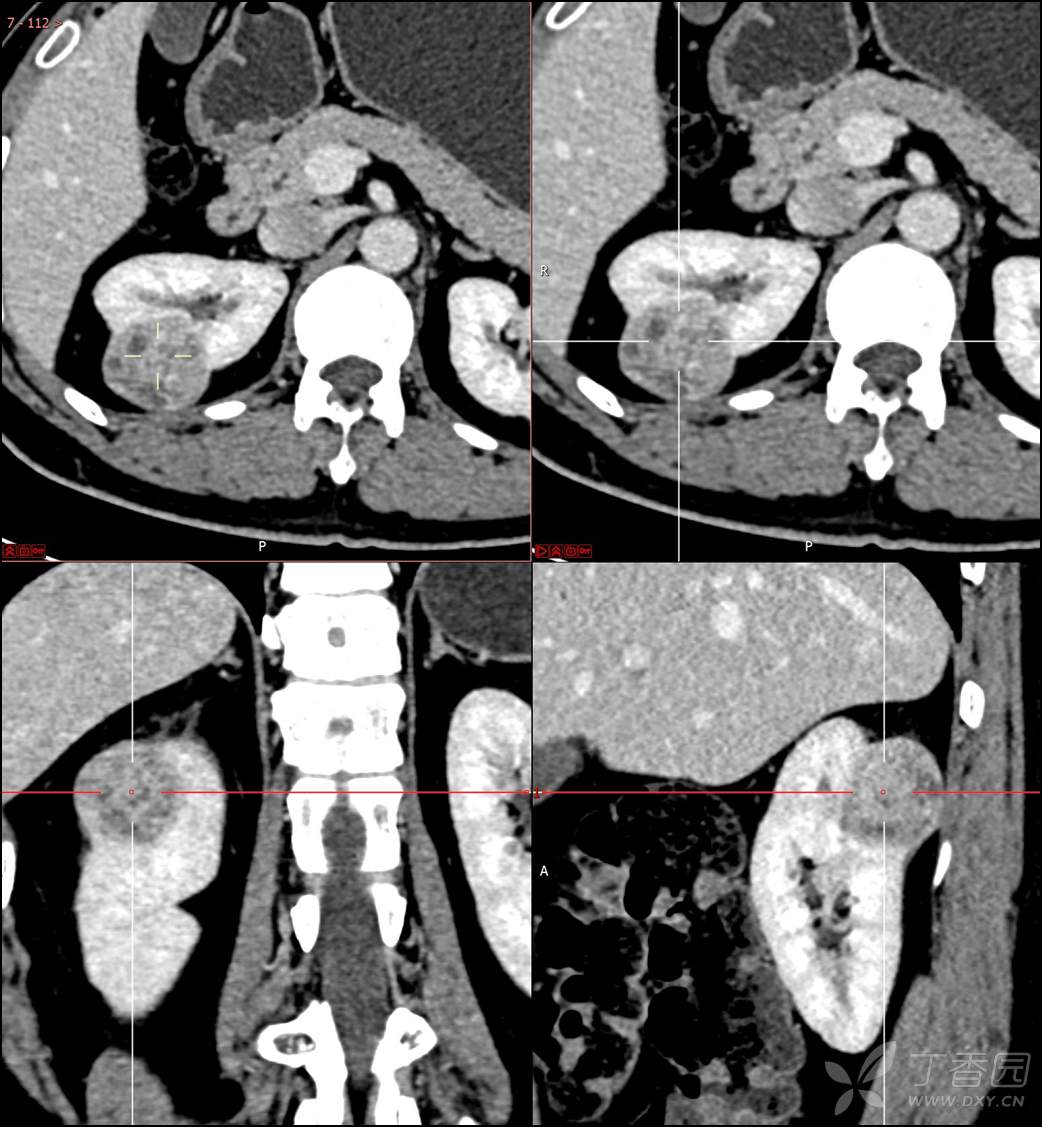

主诉:查体发现右肾肿物2月余

简要病史:患者2月余前于我院行健康查体,胸部(肺)CT平扫示:右肺中叶结节并右侧阻塞性肺炎;左肺上叶小结节;右肾占位。自诉无腰背部疼痛不适,无尿频、尿急、尿痛,无肉眼血尿,无恶心呕吐,无心悸、胸闷,无发热、寒战等不适,建议进一步检查。现患者为求进一步诊治于为我院就诊,建议手术治疗,门诊遂以“肾肿物(右)”收入院。患者自发病以来神志清,精神可,饮食可,睡眠欠佳,大便正常,体重近期无明显增减。